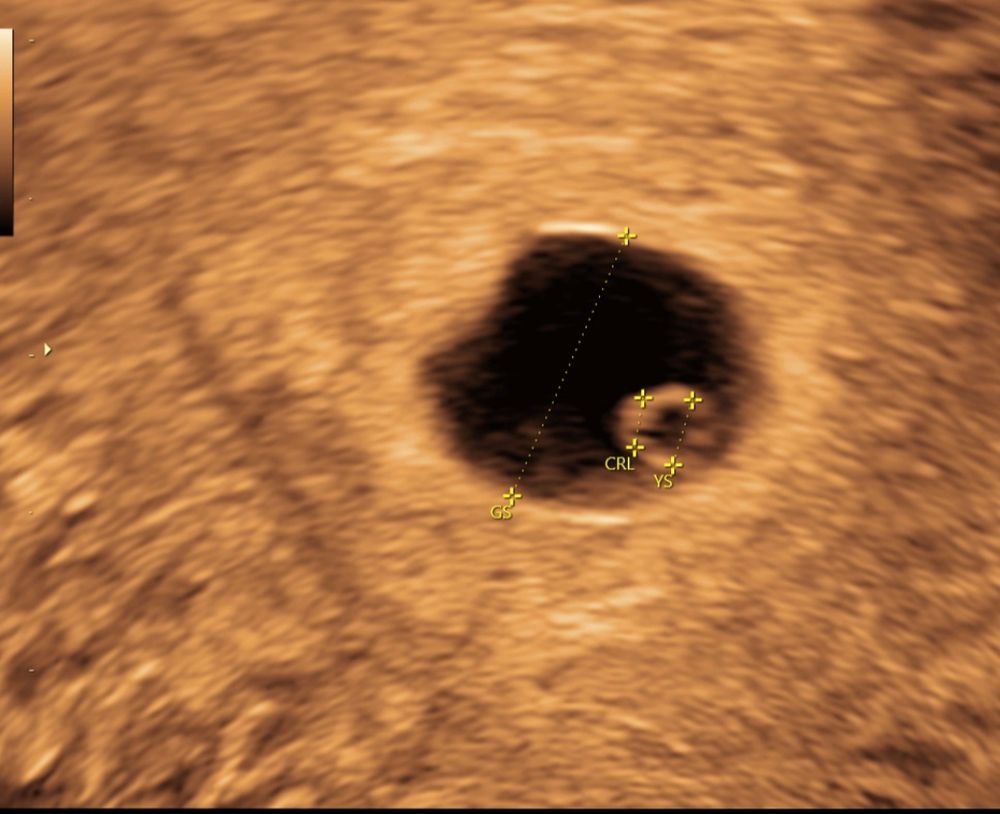

В итоге, садимся мы на УЗИ аппарат. Находит "врач" плодное яйцо, а оно пустое... У меня понятное дело паника, говорю может у вас с аппаратом что то не то? (Качество картинки было в разы хуже). На что врач зачитала мне лекцию "большинство беременностей заканчивается выкидышами, и ты не исключение, УЗИ плохое, аппарат у меня лучший, так что в понедельник контрольный прием и потом будем решать что делать (чистка).

Я очень надеялась что моя чуйка и хгч (которое растет) меня не подводит поехала сразу к первому врачу. Меня проверили и в сложном яйце все на месте и все хорошо. Вывод из истории я больше не ищу врача! А остаюсь с первым. А таким "специалистам" с плохой техникой руки бы пообрывать. Или научиться сообщать новости.... Прикрепляю фото УЗИ с разницей в 20 минут (на разных аппаратах) . Боюсь представить сколько таких беременностей было объявлено развивающимся.